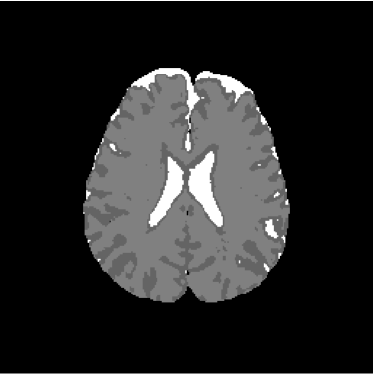

Refer to caption

Figure 14: Ground truth image (13th slice) generated by polynomial net classification

Consequently, the measured similarities between the results obtained by the use of 4-degree and 3-degree polynomial classification related to the 2-degree classification were 0.9816 and 0.9904, respectively. Therefore, we have chosen the result obtained by the 2-degree polynomial classification.

The polynomial net is a 2-layer network, where the first layer is a multiplicative net responsible for the generation of all 2-degree polynomial terms associated to 3 inputs; the second layer is an one-layered perceptron with initial learning rate η0=0.1subscript𝜂00.1\eta_{0}=0.1, training error ϵ=0.05italic-ϵ0.05\epsilon=0.05, and maximum of 200 training iterations. The second layer is responsible for the calculation of the coefficients of the polynomial dedicated to model the discriminant function of each class of interest [39, 41]. Hence, the polynomial net is a polynomial approximator. Learning rate and training error were empirically defined.